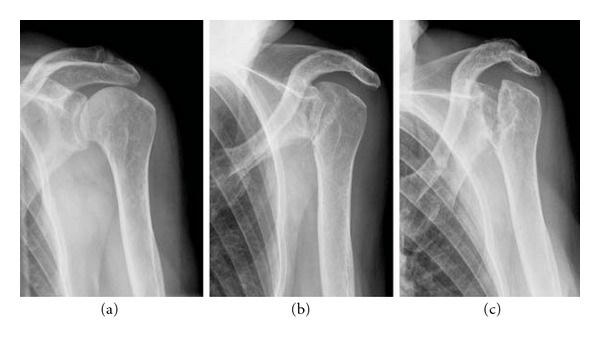

Người phụ nữ này bị đau dai dẳng cánh tay và vai trái khiến cô gặp một số khó khăn khi vận động, sinh hoạt nên cô quyết định đi khám. Sau khi tiến hành chụp chiếu, tia X cho thấy phần xương tròn kết nối cánh tay với vai của cô đã tiêu biến khiến nó chỉ còn một mảnh nhỏ. Các bác sĩ tại Viện Khoa học Y khoa Pondicherry ở Ấn Độ đã cho xét nghiệm nhiễm trùng, nội tiết tố cũng như trao đổi chất, tuy nhiên mọi thứ đều ở trạng thái bình thường.

Cuối cùng, sau 18 tháng ròng, các bác sĩ cũng có câu trả lời. Bằng cách quan sát các ảnh chụp X-quang, họ nhận thấy cấu trúc xương trong cơ thể người phụ nữ mờ dần sau mỗi lần tái khám. Nhiều xét nghiệm được tiến hành và cũng xác nhận rằng xương của bệnh nhân biến mất đúng theo nghĩa đen. Tuy nhiên, các mạch máu lại tăng trưởng thay thế cho mô xương của cô. Thậm chí, các bác sĩ còn nhận thấy vai của cô dẻo như cao su, có thể xoay cánh tay “180 độ” như người không xương mà không gặp chút khó khăn hay đau đớn gì.